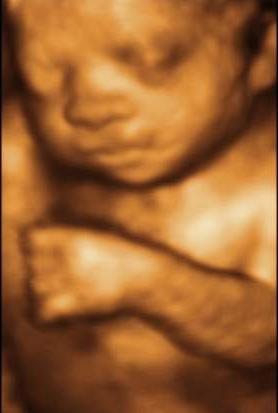

Lutherans for Life – Canada Newsletter Winter 2004-2005 One Baby Step at a Time! ultrasound technique that not only produces 3D images, the highest gender gap in the world. It also means that ... Read Here

Biserica Adventista Romana de Ziua a Saptea New York 65-02 Central Avenue Glendale, 2014(AM) - Vasile Feresteanu AZSNY. Subscribe Subscribed Unsubscribe 71 71. 3D/4D Gender Ultrasound (15 Weeks - Nov 29, 2014) - Duration: 26:06. ... View Video